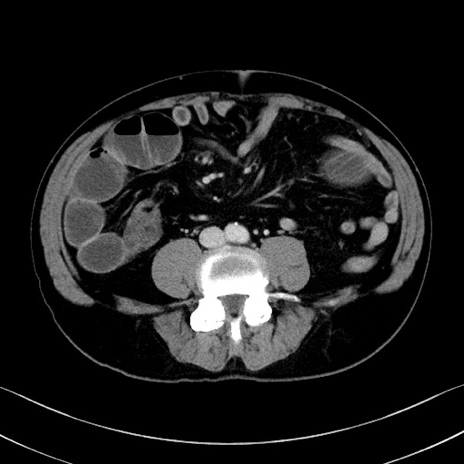

症例35(横断像)

冠状断像

【症例】70歳代 男性

【主訴】腹部膨満、嘔吐

【現病歴】昨日より腹部膨満感出現。本日増悪し、仙痛出現。嘔吐あり、受診。

【既往歴】糖尿病、胆摘後

【身体所見】BP 149/80mmHg、HR 74/min、BT 35.9℃、腹部:膨満、軟、圧痛なし。腸雑音減弱あり。上腹部正中切開瘢痕あり。

【データ】WBC 13500、CRP 1.72